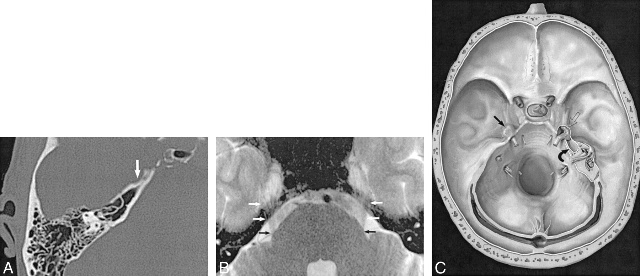

1. 体位、切口、骨窗病例均采用后颅窝旁正中直切口或钩性切口,34例采用乳突后缘直切口。侧卧位,患侧朝上,在乳突后缘作直切口6~8cm,切口上端平耳尖,下端平耳垂,逐层切开达枕鳞,充分暴露后,在枕鳞钻孔,扩大骨窗为3×3cm2,骨窗上缘达横窦,外侧达乙状窦的上段,尽量不打开乳突气房,否则开放的乳突气房用骨蜡封闭。

手术路径:一般分为枕下径路、耳后径路(迷路后和乙状窦后入路)。枕下入路视野广,但损伤大,并发症多。迷路后径路视野小,给手术成了很大困难。乙状窦后入路视野宽,适应症广,并发症较少,相比之下,优点较多,为理想的手术路径。